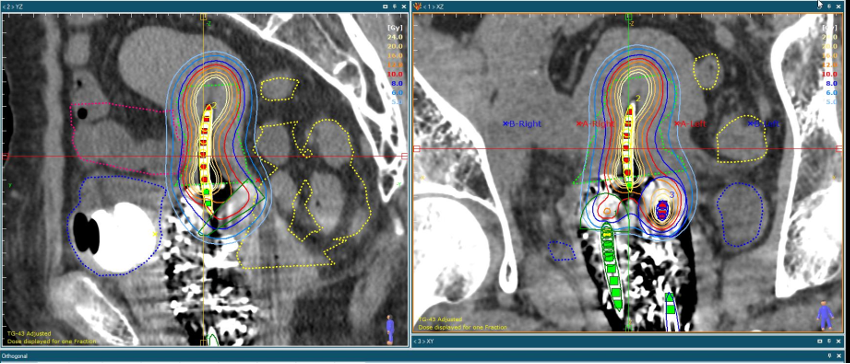

腔内照射(密封小線源治療)は体内に放射線源を入れて病変部の近くから照射する治療法です。当院では子宮癌などの婦人科癌に対して行っています。子宮と膣内にアプリケーターと呼ばれるチューブを留置し、その内部に数㎜の線源(放射性物質)を腫瘍付近に遠隔操作で挿入して腫瘍に集中的に照射する方法です。用いられる放射性物質はイリジウムです。

毎回の治療時間は1時間ほどかかります。通常4-6回照射します。